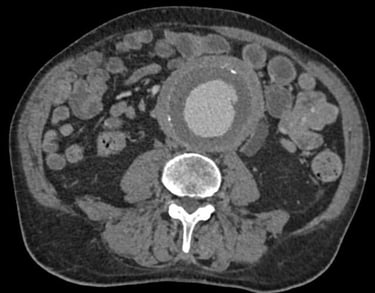

Nel caso di dubbi o approfondimenti diagnostici, può essere eseguita una tomografia computerizzata (TC) con mezzo di contrasto